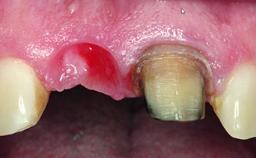

Replacement of a Failing Upper Left Central Incisor: Immediate Placement of an RC Bone Level Implant and Provisionalization

A healthy 23-year-old female patient was referred for a consultation on replacing tooth 21 with an implant-supported restoration. The patient had recently moved to the area and reported a history of endodontic and periodontal treatment for tooth 21. The tooth had been deemed non-restorable by her previous periodontist but since she was going to be moving, he recommended consulting to a dentist in her new city to continue her treatment. A review of her medical history yielded no significant findings and no known drug allergies. The analysis of her smile revealed a medium to high symmetrical smile line and a slightly discolored tooth 21.

Placement Protocol Immediate implant placement

Tooth Site Maxillary incisor or canine